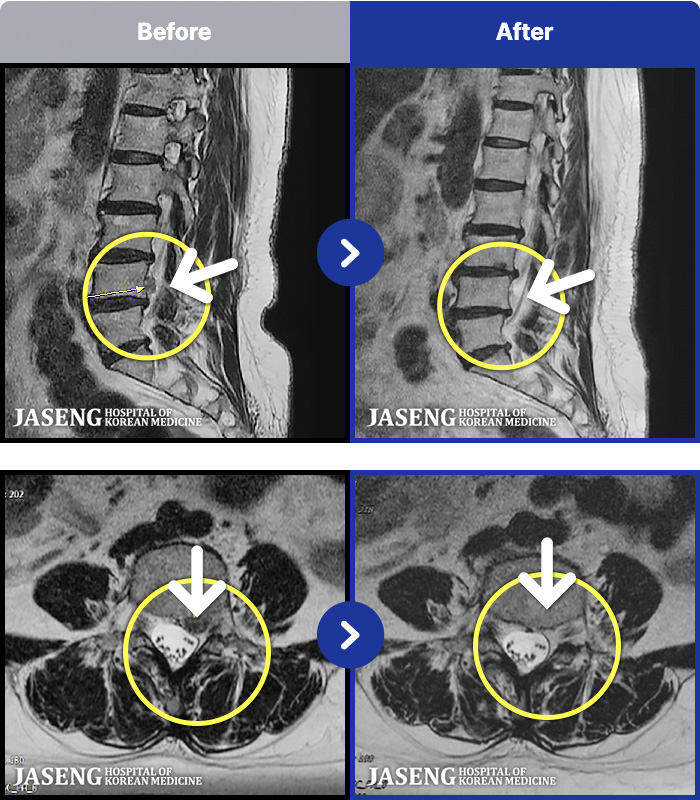

[ϻ] 24.07.25~25.08.01

ȯںп Ǹ ǿ ԿǾ, ο ġ ۿ Ƿ ġḦ Ͻñ ٶϴ.